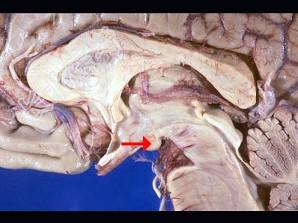

- 单项选择题如图箭头所示为大脑哪个部位 ( )

A、前连合

B、后连合

C、室间孔

D、乳头体

E、垂体